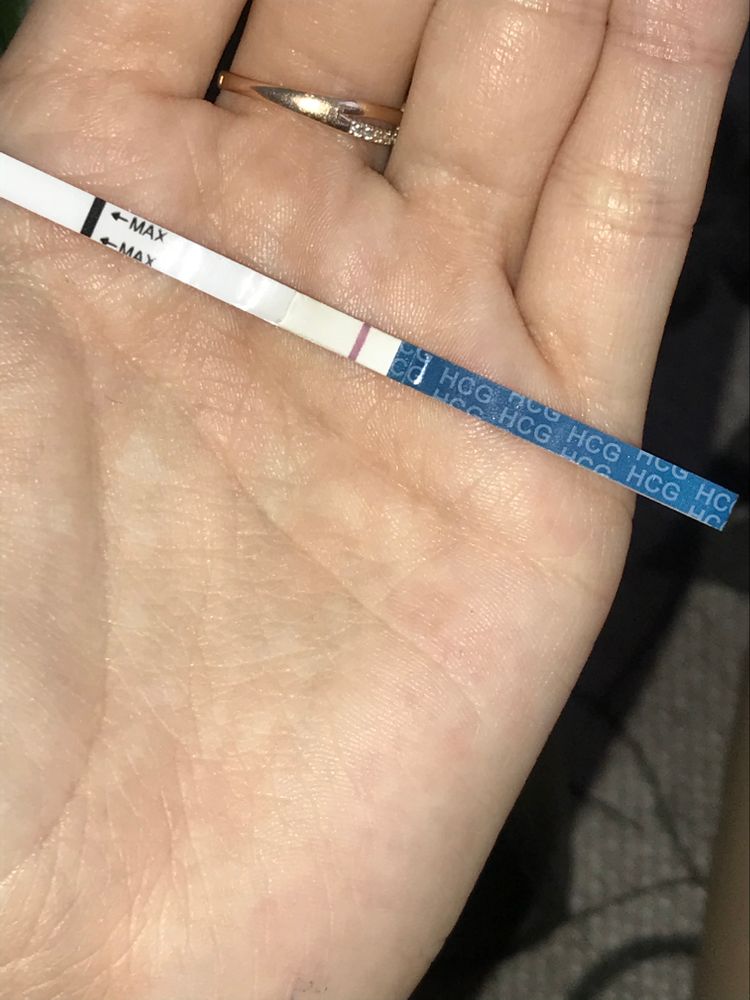

Что видите ?

Вчера закончились месячные,но были подозрения и решила сделать тест.

Вижу только одну,а вы ?

Вчера закончились месячные,но были подозрения и решила сделать тест.

Вижу только одну,а вы ?

Девочки,что видите вы ? Видим плюс или кажется ?